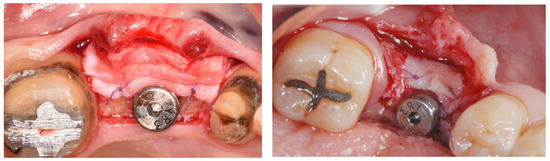

4. Discussion

5. Conclusions